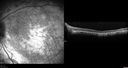

80 year old man Diagnosed at age 12 with retinitis pigmentosa. His central vision has been poor for a long time. He had surgery for nystagmus 3 times. He has worn glasses ever since he was 3 and he was bumping into walls when he was little. Night blindness was noticed by his mother at a young.

Mutations were confirmed in NR2E3 (Enhanced S Cone Syndrome)

VA OD HM; OS 6/200